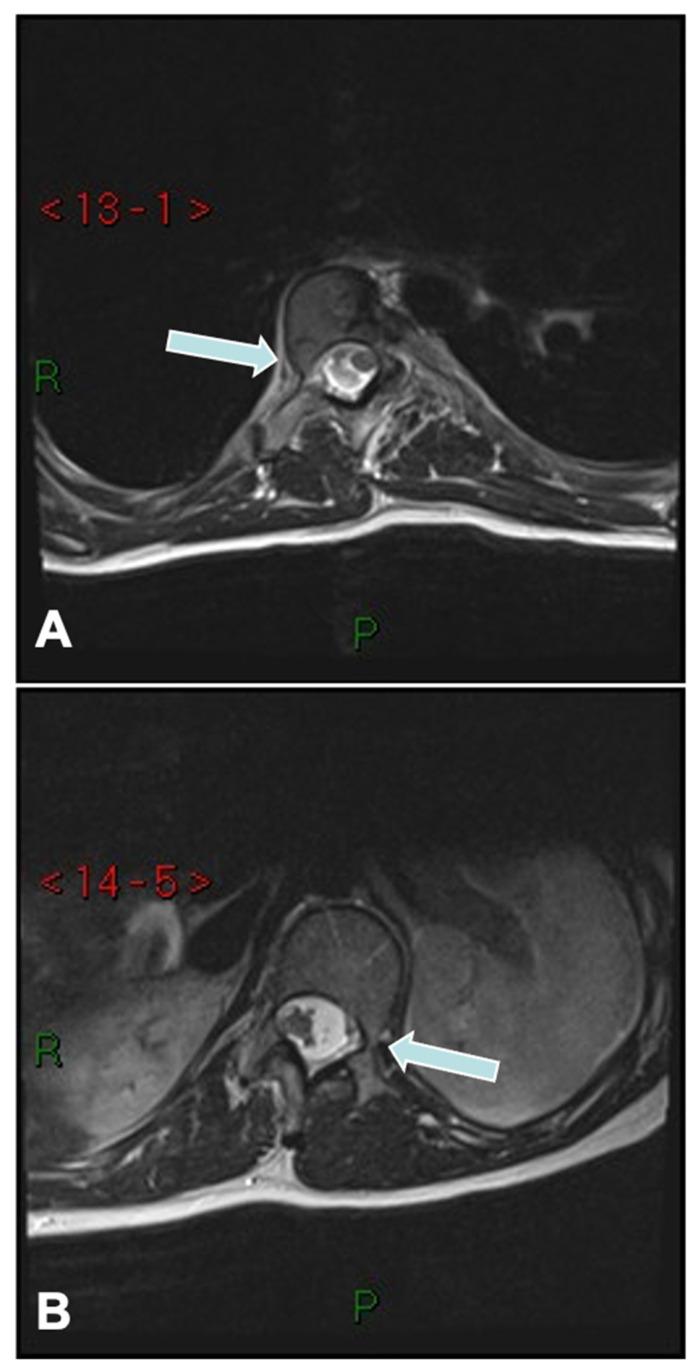

Surgical management of adolescent idiopathic scoliosis [AIS] is a complex undertaking with the primary goals to correct the deformity, maintain sagittal balance, preserve pulmonary function, maximize postoperative function, and improve or at least not harm the function of the lumbar spine. The evolution of surgical techniques for AIS has been remarkable, transitioning from rudimentary methods of spinal correction to highly refined, biomechanically sound procedures. Modern techniques incorporate advanced three-dimensional correction strategies, often leveraging pedicle screw constructs, which provide superior rotational control of the vertebral column. A number of surgical techniques have been described in the literature, each having its own pros and cons. This narrative review provides a detailed analysis of the contemporary surgical techniques used in the treatment of patients with AIS.

青少年特发性脊柱侧凸(AIS)的外科治疗是一项复杂的工作,主要目标是矫正畸形、维持矢状面平衡、保留肺功能、使术后功能最大化,以及改善或至少不损害腰椎功能。AIS外科技术的发展十分显著,已从基本的脊柱矫正方法转变为高度精细、生物力学合理的手术。现代技术采用先进的三维矫正策略,常利用椎弓根螺钉结构,从而对脊柱提供更好的旋转控制。文献中描述了多种外科技术,每种技术都有其优缺点。本叙述性综述对治疗AIS患者时使用的当代外科技术进行了详细分析。